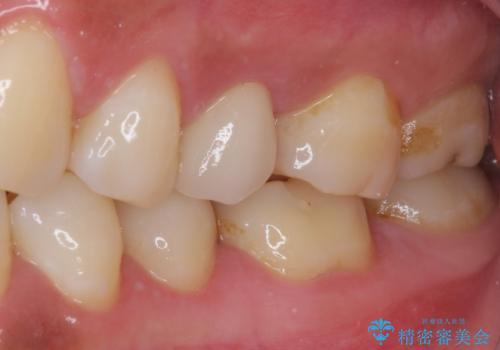

- 上下の歯が接触する度に痛みを感じるとのことで来院された患者様です。

診査の結果、既に歯の神経は失活しており、レントゲンより根尖部に病変を認めました。

根管治療を行った後にオールセラミッククラウンにて補綴することとしました。